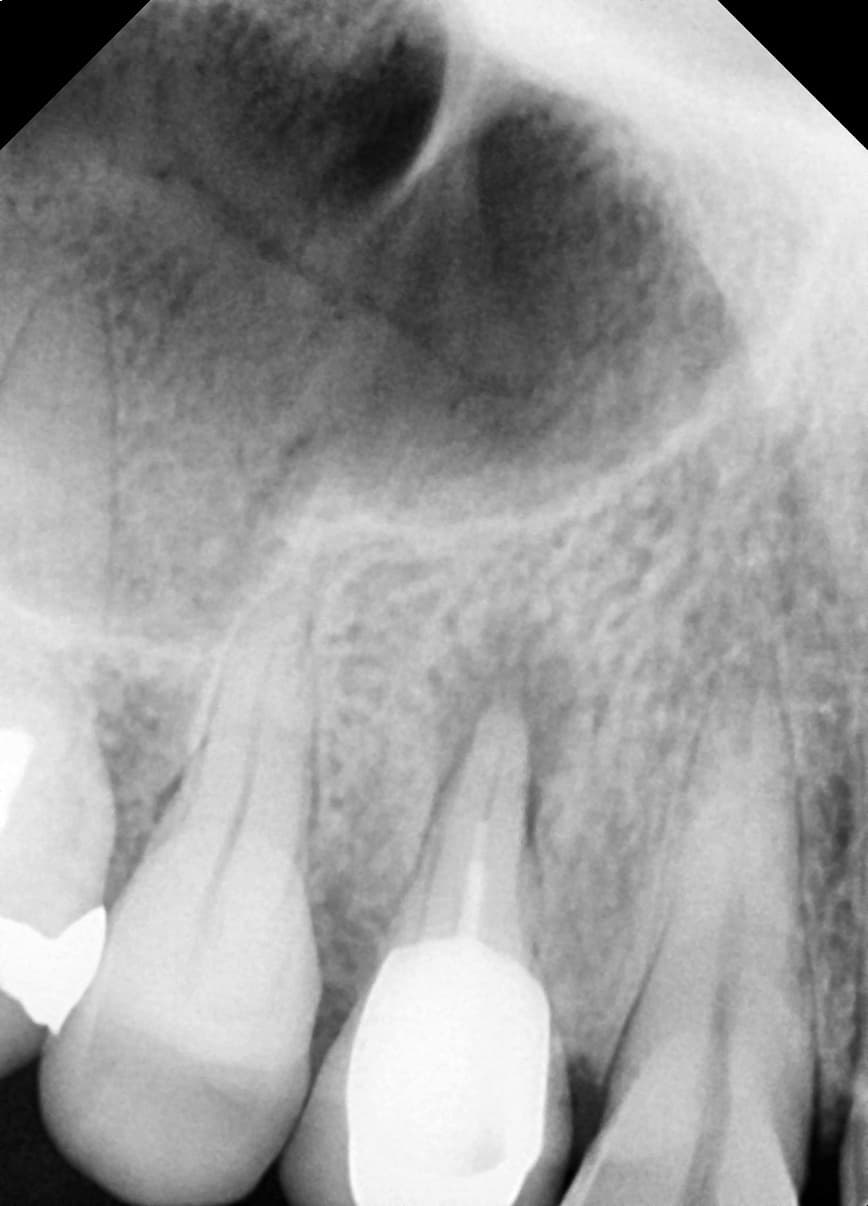

치근단절제술

뿌리 끝까지 염증이 번진 앞니

Before

After

재신경치료 및 치근단절제술 후 병소 완치